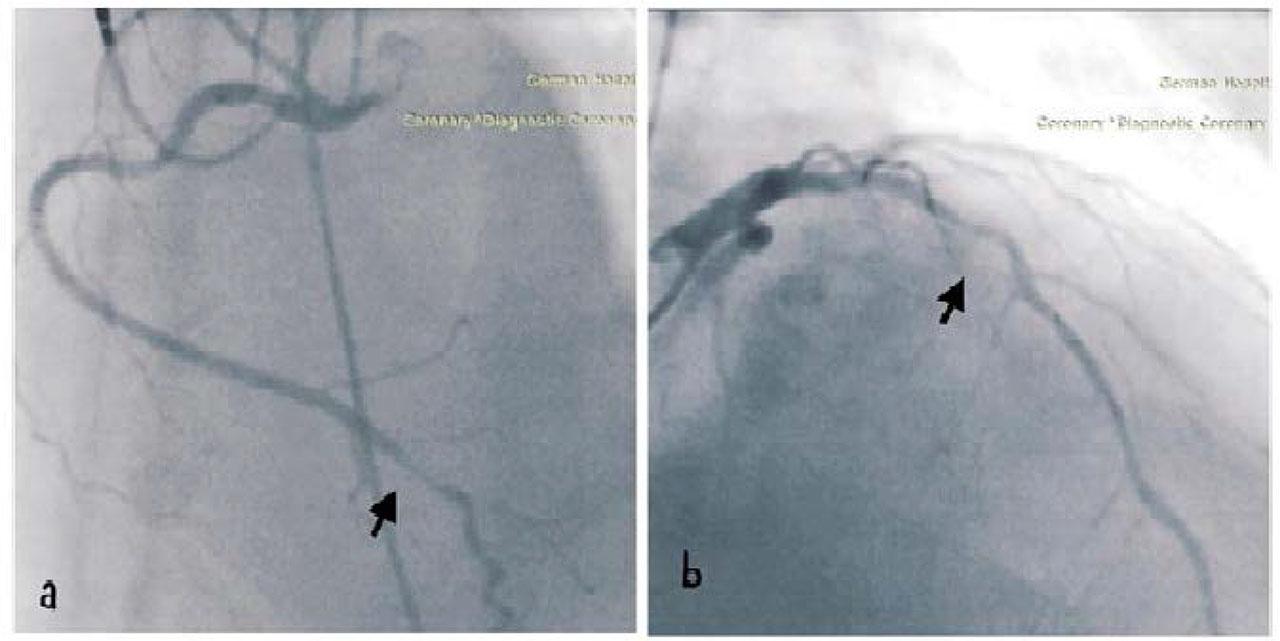

The following day, a permanent dual-chamber pacemaker (DDDR) was implanted. After 48 hours of intravenous fluids to mitigate contrast-induced nephropathy risk, a coronary angiogram was performed. This revealed 90% stenosis in the distal tract of the right coronary artery (RCA) and 75–90% stenosis in the proximal tract of the left anterior descending artery (LAD). Both stenoses were addressed with percutaneous coronary intervention using two drug-eluting stents. Figure 4

(a) Right coronary artery (RCA) distal tract stenosis (90%), (b) Left Anterior descendent artery (LAD) medial tract stenosis (75–90%)